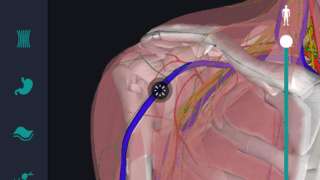

はじめに 本記事では、人体解剖学における専門的な部位の知識を始めに、効果的な勉強法についてご説明します。 人体解剖学では様々な器官や筋肉、骨の名称を覚えるだけではなく、体のどの位置に存在するのかまで覚えなければなりません。そのため、できるだ...